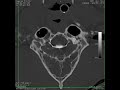

páteř / nádorové onemocnění

Nádorové onemocnění krčního úseku páteře u psa 10 let

Tumor v páteřním kanále po operaci údajné vyhřezlé ploténky.